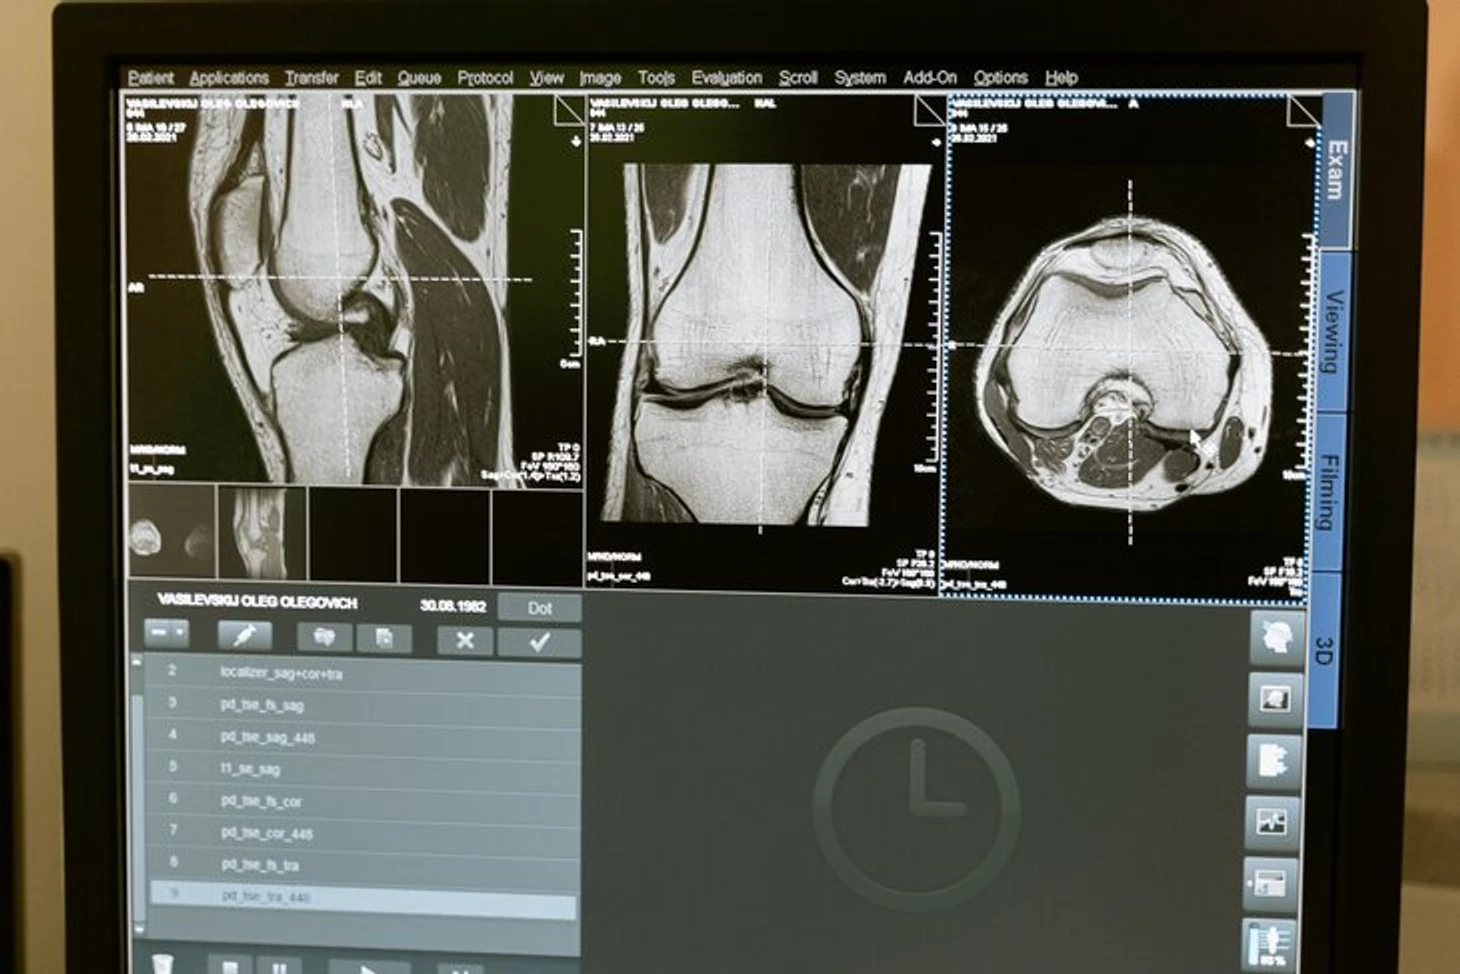

Среди инструментальных исследований при диагностике заболеваний коленного сустава информативными являются:

КТ, МРТ;